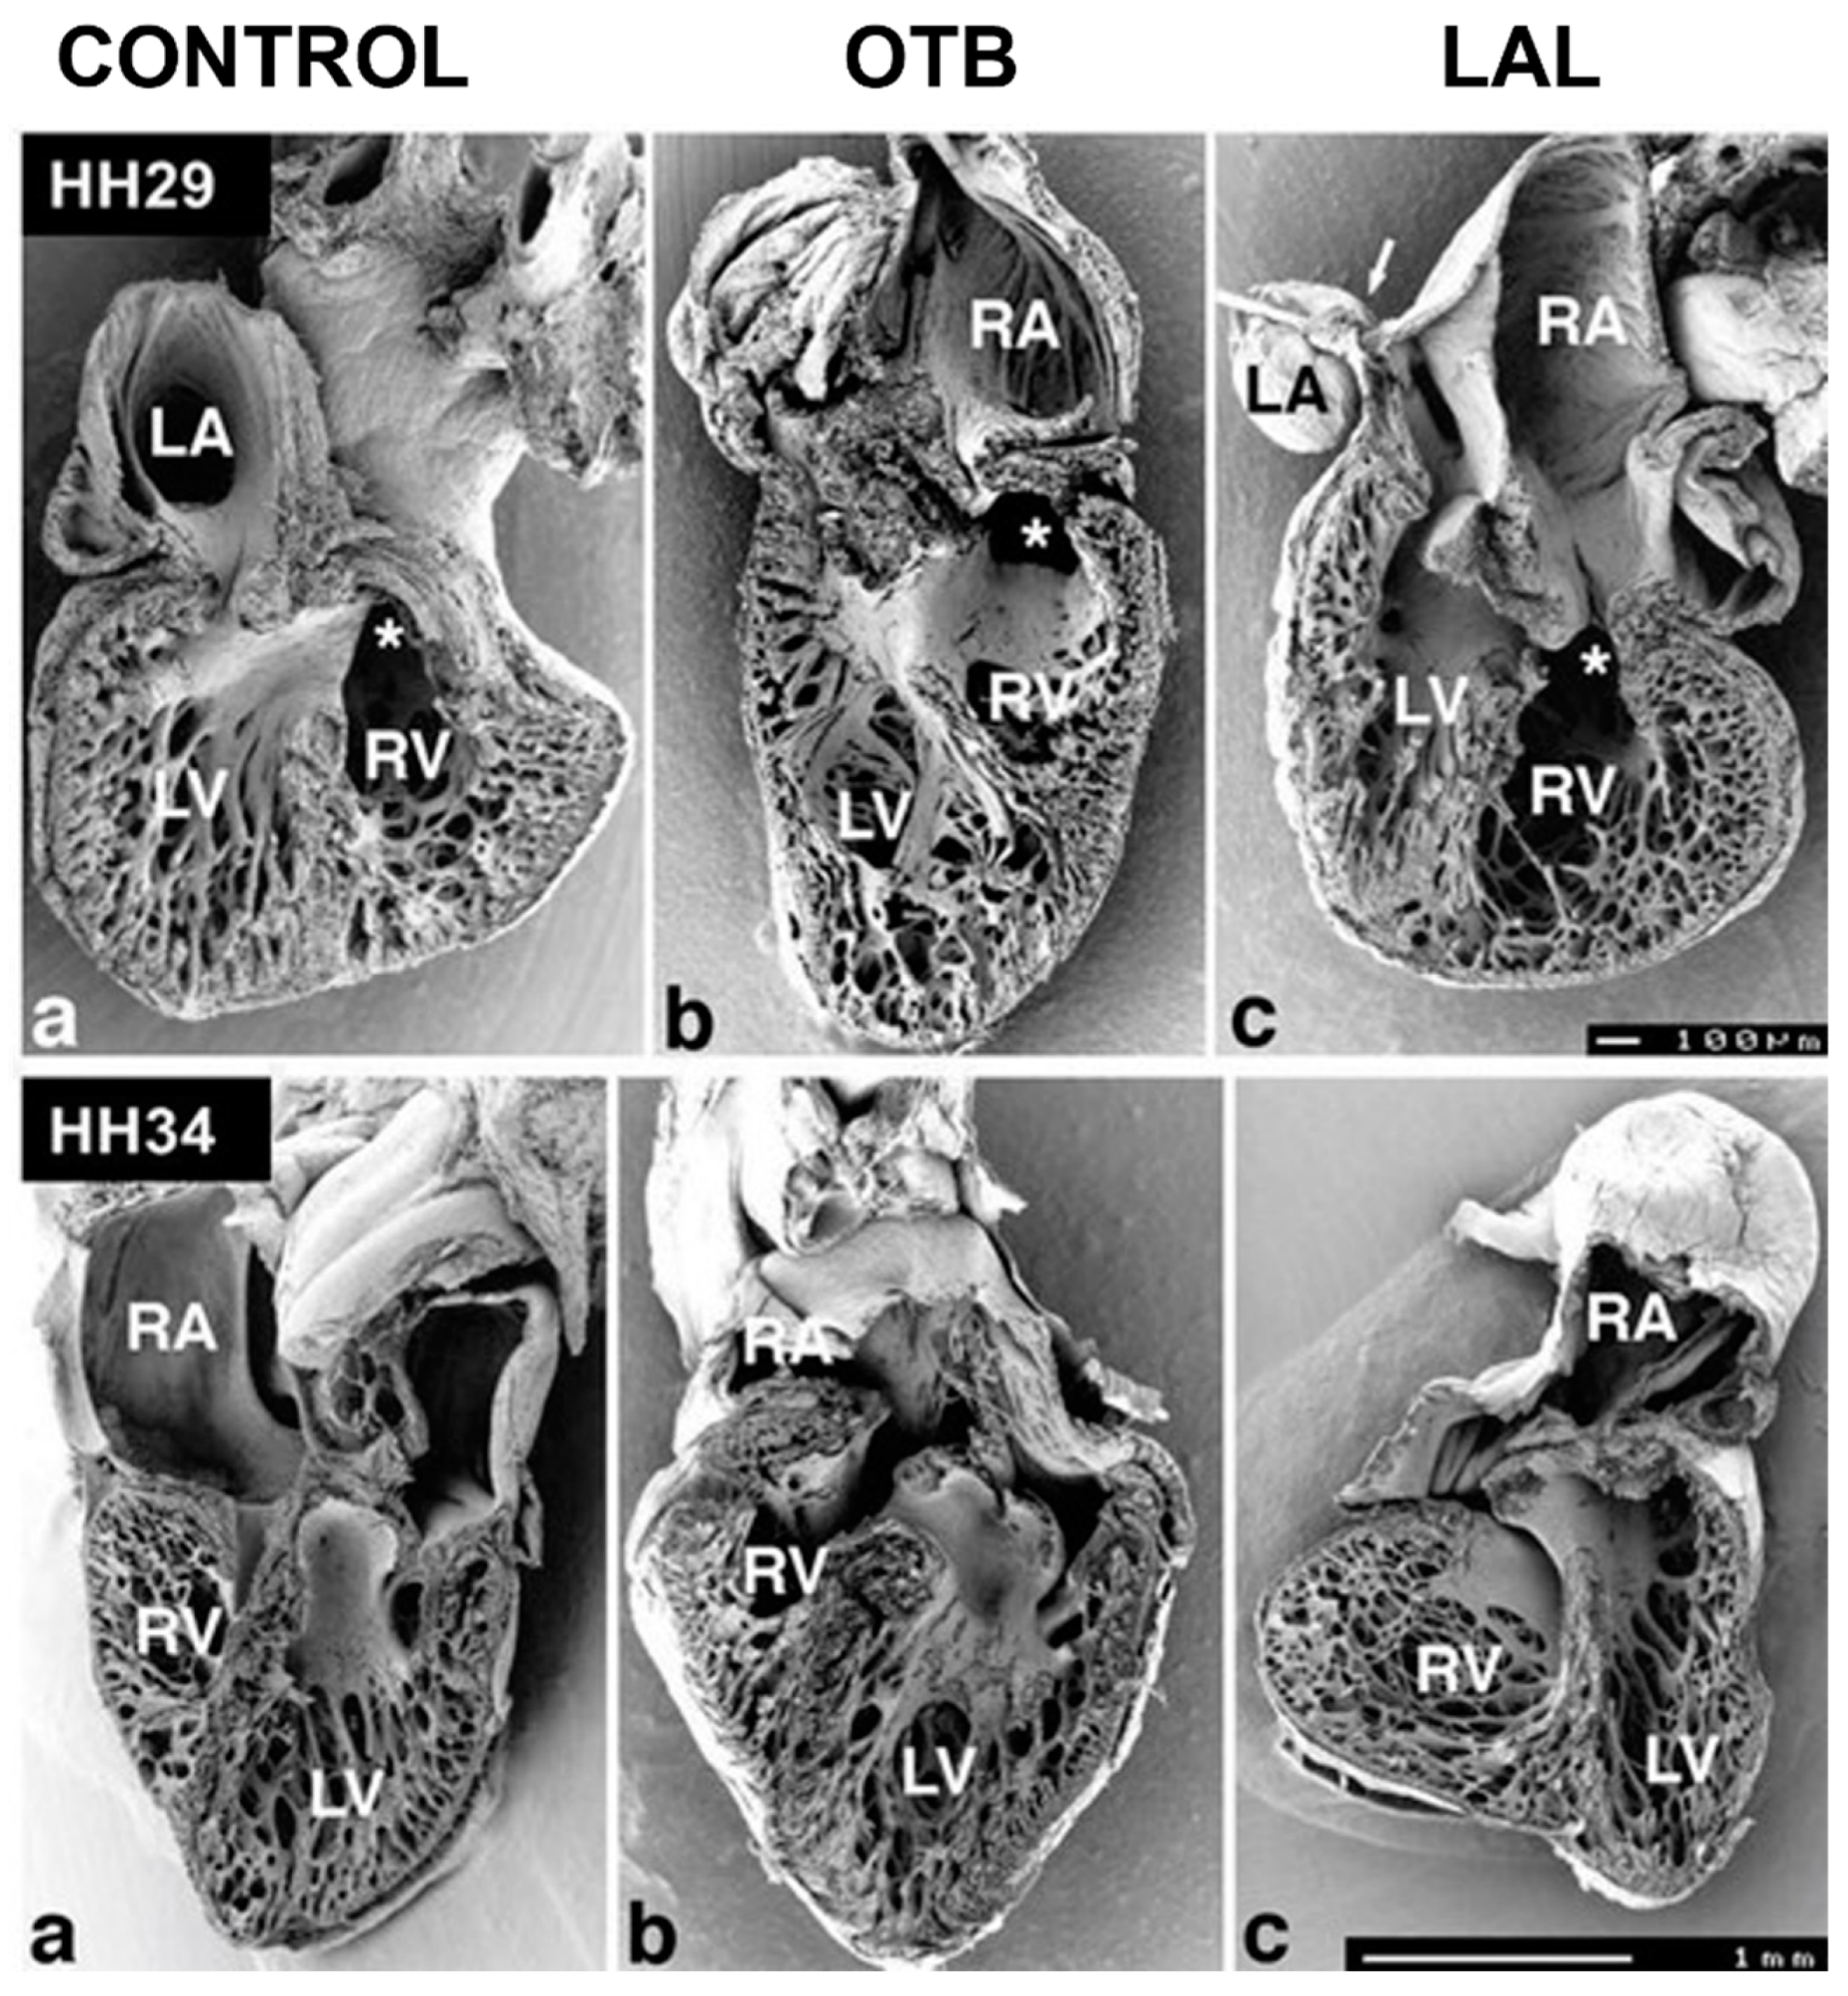

5.2. Ventricular Formation

- Sedmera, D.; Pexieder, T.; Rychterova, V.; Hu, N.; Clark, E.B. Remodeling of chick embryonic ventricular myoarchitecture under experimentally changed loading conditions. Anat. Rec. 1999, 254, 238–252. [Google Scholar] [CrossRef]

- De Almeida, A.; McQuinn, T.; Sedmera, D. Increased Ventricular Preload Is Compensated by Myocyte Proliferation in Normal and Hypoplastic Fetal Chick Left Ventricle. Circ. Res. 2007, 100, 1363–1368. [Google Scholar] [CrossRef]